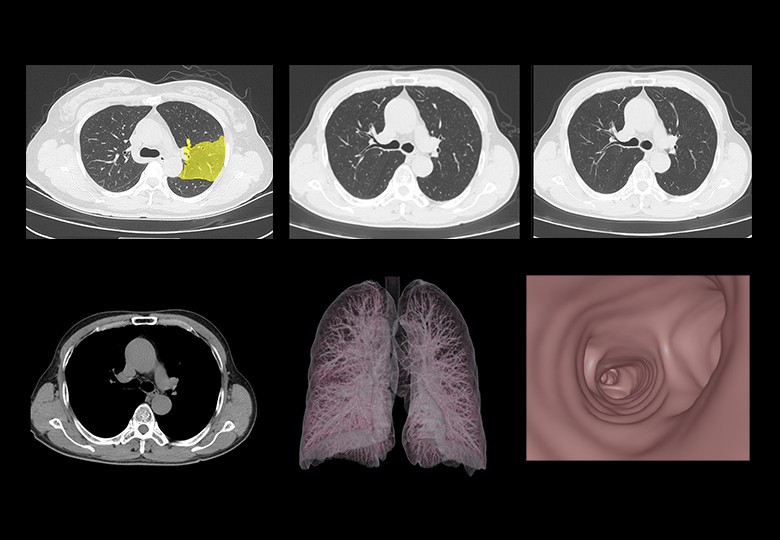

Album d'images cliniques

• Poumon